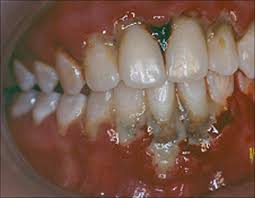

O sinal mais marcante é a necrose das papilas interdentais, frequentemente descrita como uma aparência em “cratera”, resultado da destruição tecidual localizada. Sobre essas áreas necrosadas, observa-se a formação de pseudomembranas acinzentadas ou esbranquiçadas, que recobrem as lesões e podem ser facilmente removidas, revelando um tecido subjacente intensamente dolorido e sangrante.

O sangramento gengival ocorre de forma espontânea ou ao mínimo contato, refletindo o grau de inflamação e fragilidade vascular local.

Nos casos mais avançados, os sintomas extrapolam a cavidade oral.

Pode ocorrer linfadenopatia dolorosa em região submandibular e cervical, acompanhada de febre, mal-estar geral e aumento de sialorreia, indicando comprometimento sistêmico.